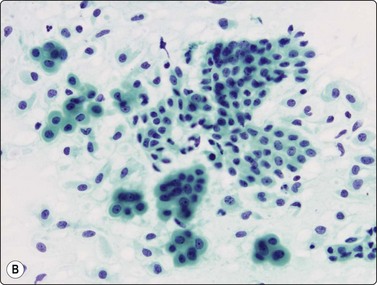

image image image

Fig. 8.28 High-grade neuroendocrine carcinoma; small cell carcinoma

(A, B) Smears showing ‘intermediate’ morphology. Loose aggregates of fragile cells with traumatization artifact and nuclear molding but some background cytoplasm (A, Pap, MP; B, H&E, HP). (C) Tissue section of resected peripheral stage 1 small cell carcinoma (H&E, HP).

Cell pleomorphism is so distinctive that a diagnosis of malignancy is seldom in doubt (Figs 8.25-8.27). The most immediate impression is the absence or sparseness of cytoplasm rather than the small size of the neoplastic cell (Figs. 8.26 and 8.27). In fact, the cell nuclei may appear larger than similar cells in sputum and this may mislead one into making a diagnosis of non-small cell carcinoma. This difference in size between sputum and aspirated material is due to degenerative changes and shrinkage in sputum. It is sparseness of cytoplasm rather than size which is the most helpful initial clue in differentiating the lesion from other pulmonary carcinomas.

The combination of dispersal with clustering is also important, especially when other small cell neoplasms enter the differential diagnosis (Fig. 8.25). Lymphomas generally do not display such cell cohesion, although large fragments may be dislodged, and in some cases lymphoid cells may form clusters or packets.

Fragility of nuclei is emphasized by tear-drop cells or streaks of smeared nuclear material,226 and the close nuclear apposition and molding so commonly seen in sputum are also evident (Figs 8.26 and 8.27). Uniform coarsely granular ‘salt and pepper’ nuclear chromatin is also a well-recognized feature of this cancer in other sites, but one point of difference from sputum is the frequency of small nucleoli in aspirated material; they are less commonly seen in sputum. This may also be related to the better preservation of cells removed directly from tumor; small nucleoli are also often seen in bronchial brush material. Mitotic figures are usually easily found.

Although ‘intermediate’ small cell carcinoma is no longer recognized as a separate category in international classifications, we find it a useful concept to highlight the occasional difficulty in distinguishing between small cell and poorly differentiated non-small cell carcinomas (Figs 8.28 and 8.29). There is overlap in nuclear size between small and large cell carcinomas and a tendency for inexperienced cytologists to include small cell carcinomas with larger than expected nuclei in the non-small cell category. In general, if the nuclear features of a problematical tumor are those of small cell carcinoma – that is, granular chromatin without prominent nucleoli – the neoplasm will usually fall into the small cell carcinoma group histologically, whereas vesicular nuclei with prominent nucleoli would generally be evidence of non-small cell tumor. However, large cell neuroendocrine carcinoma does provide special problems. Our experience is limited but is similar to Yang et al. who described various morphologic patterns in this family of tumors, including small cell-like and mixed small cell/large cell-like FNAC patterns.37 Cell size is therefore an important criterion and one to be critically evaluated. Tumors with nuclei larger than 2–3 times the diameter of a lymphocyte may be classified as LCNEC histologically, even if nuclear chromatin pattern and other cytological features are similar to those of small cell carcinoma (Fig. 8.29). Our approach is therefore to first come to a diagnosis of ‘high-grade neuroendocrine carcinoma’ and then to critically examine cell size and morphology to determine the best category – ‘small’ or ‘large’. We do, however, agree with the idea propounded by Marchevsky et al.89 that the distinction between the two categories may be somewhat artificial in view of the overlap in cell size between the two groups. This is an area which requires close cooperation with oncologists and an acceptance of the limitations of cytological diagnosis. It may be necessary to base management on clinical and staging findings in conjunction with inconclusive cytological tumor typing in some cases.